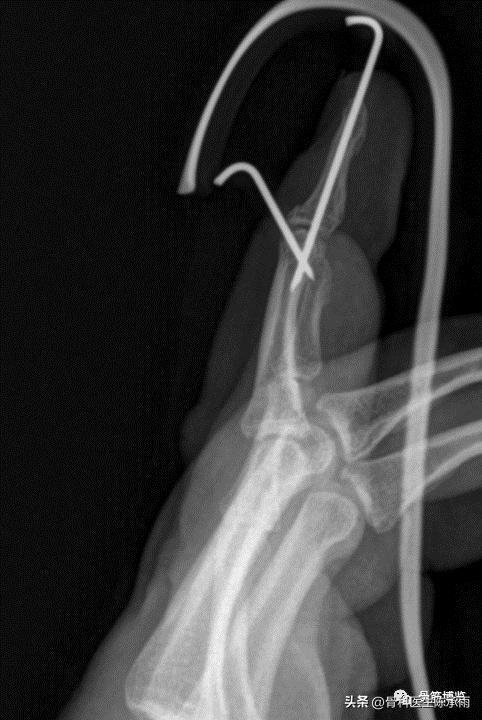

(1)经皮(不切口)背侧阻挡钉手术固定,缺点是仍有部分旋转不能矫正

(2)钢丝抽出指腹侧钮扣加克氏针固定或直接固定于克氏针上

(3)锚钉固定克氏针固定